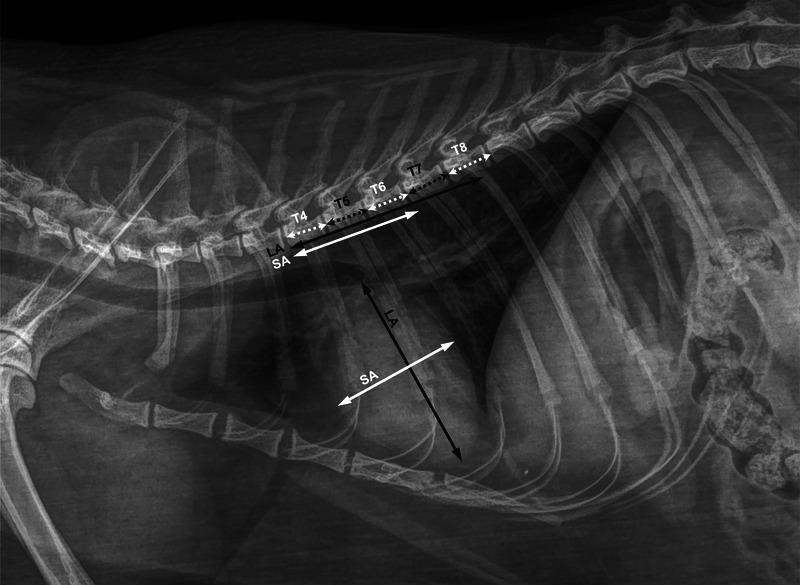

The heart-to-single vertebra ratio (HSVR) has been proposed as a simple, quick, and reliable radiographic method to assess cardiac silhouette dimensions in dogs. The HSVR shows excellent agreement with the vertebral heart size (VHS), and it can also be accurately determined in dogs with vertebral abnormalities affecting the thoracic spine. This retrospective, single-center, method-comparison, observer-agreement study investigated the reliability of the HSVR in cats. Three observers retrospectively evaluated anonymized right-lateral thoracic radiographs obtained over a set period of time. Exclusion criteria included the presence of thoracic spine alterations and the inability to outline the cardiac silhouette. The HSVR was calculated by dividing the sum of the cardiac long and short axes by the length of each vertebral body from T4 to T8. Images of 101 cats of different breeds met the inclusion criteria. Lin's concordance correlation coefficient and the relative 95% confidence interval (CI) revealed that the HSVRT6 showed the best agreement with the VHS (0.95; 95% CI: 0.91-0.97). Bland-Altman plots showed low bias (-0.023 ± 0.19; limits of agreement = -0.39 to 0.35) between the HSVRT6 and the VHS, with low mean absolute error (0.14; 95% CI: 0.12-0.17) between the two methods. The intraclass correlation coefficients, evaluated on 20 cats, demonstrated excellent interobserver agreement (0.95-0.96; p < .001) and good to excellent intraobserver agreement (0.75-0.94; p < .001) for all HSVRs. The results of this study confirmed that the HSVR is a simple, quick, and reliable alternative to the VHS also in cats.